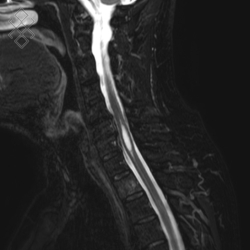

IRM Médullaire

Pour une IRM médullaire, aucune préparation n'est requise. Dans le cas d'une injection du produit de contraste, un cathéter vous sera posé par le personnel soignant. De même, en fonction de votre âge, le centre vous prescrira une prise de sang pour évaluer le taux de créatinine.

La durée moyenne de l'examen est de 25 min. Dans le cas d'une injection, le manipulateur en radiologie vous administrera le produit de contraste. Vous entendrez un bruit caractéristique à l'IRM faisant penser à un marteau piqueur.